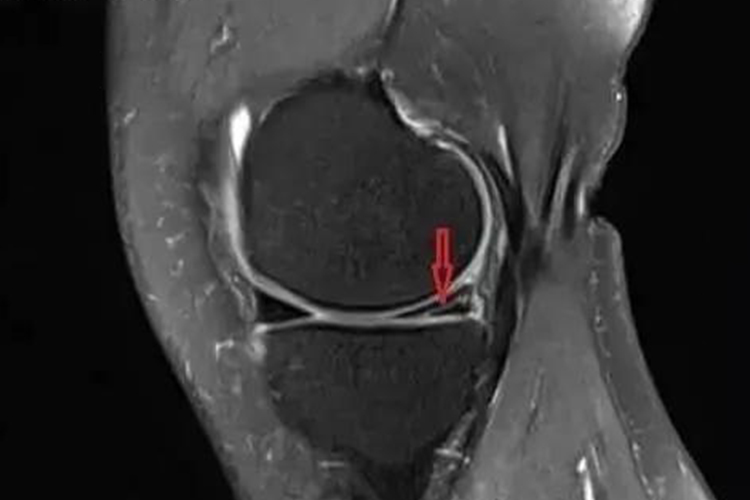

核磁共振对于半月板损伤中的撕裂、变形等情况,敏感性及特异性较高,是临床上常用的检查方法。

半月板由纤维软骨构成,在所有脉冲序列上均表现为低信号结构,核磁共振检测半月板撕裂的敏感性及特异性通常可超过90%,因此能够清晰显示出半月板有无变性、撕裂,另外还可察觉有无关节积液与韧带的损伤等情况。